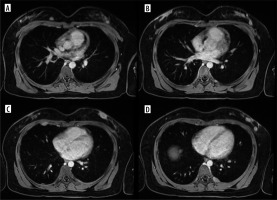

Case 2

A 15-year-old patient was admitted to our institute for further diagnosis and treatment of a sacral bone tumour. A few days earlier, she was admitted to another centre with shortness of breath, blueness of the fingers, and coldness of the left lower limb. Computed tomography (CT) of the chest, abdomen, and pelvis performed at that time revealed the following: 1) pulmonary embolism with infarction of the lower segments of the left lung; 2) partially sclerotic tumour of the sacrum with aggressive periosteal reactions, extensive periosteal masses with calcifications surrounding the sacrum, infiltrating dorsal and piriform muscles, spreading paraspinally, penetrating the spinal canal through the left intervertebral foramina L2/L3, L3/L3, and L4/L5 and metastatic foci in the L4 and L5 vertebrae; 3) tumour plugs in the vessels – inferior vena cava to the level of the right atrium, common iliac veins, internal iliac veins, left external iliac vein, smaller pelvic veins, including uterine venous plexus, and massive collateral circulation with tumour plugs (Figure 6).

Figure 6

Exams of Patient no. 2 with tumour plugs in the vessels. A, B) Computed tomography (CT) shows partial sclerotic tumour plugs in many vessels, including uterine venous plexus. A) Coronal plane, B) axial plane. C) CT scan shows chondrosarcoma of the sacrum; axial plane. D) MRI study; STIR, coronal plane

After the biopsy low-grade central chondrosarcoma was diagnosed.

In case of chondrosarcoma, the metastatic disease has limited treatment options due to the poor sensitivity of the tumour to chemotherapy and radiotherapy. No standard chemotherapy regimens exist for advanced and metastatic disease [28]. Our patient with unresectable, metastatic chondrosarcoma of the sacrum initially received systemic treatment (chemotherapy), and then she was qualified for and received targeted therapy. The complicated chemotherapy regime in her case was as follows: cycle 1 – ADM (adramycin), cycle 2 – AP (doxorubicin + cisplatin), cycles 3-4 – AI (doxorubicin + ifosfamide), cycles 5-6 – ifosfamide, cycles 7-9 – AI, and cycles 10-11 – IFO (ifosfamide); between cycles 10 and 11 pazopanib was introduced. Subsequently, second-line chemotherapy was initiated – VP (etoposide + carboplatin). Radiotherapy of the primary tumour was also performed between cycles 5 and 6. During the treatment, pulmonary embolism occurred, with a massive embolus filling the left pulmonary artery and the right atrium. Initially, conservative treatment was started (Clexane), but due to lack of clinical improvement, it was decided to evacuate the clots surgically. The embolic material was found to be chondrosarcoma. Positron emission tomography–computed tomography (PET-CT) revealed metabolic reactivation of metastatic foci in L4 and L5 vertebral bodies. The patient was given 2 new targeted drugs - pembrolizumab and cabozantinib, but shortly after starting this treatment the patient suddenly died.

To the best of our knowledge, only one case of secondary involvement of the reproductive system by chondrosarcoma has been described so far. It was an 18-year-old patient with chondrosarcoma of the ribs and metastasis to the left ovary [22], while interestingly in the context of this manuscript, a few cases of primary breast chondrosarcoma have been published [29]. Even more interestingly, we found a case report of intravascular pulmonary tumour embolism 3 years after complete resection of sternal chondrosarcoma, in a way resembling our case, but without calcifications [30].